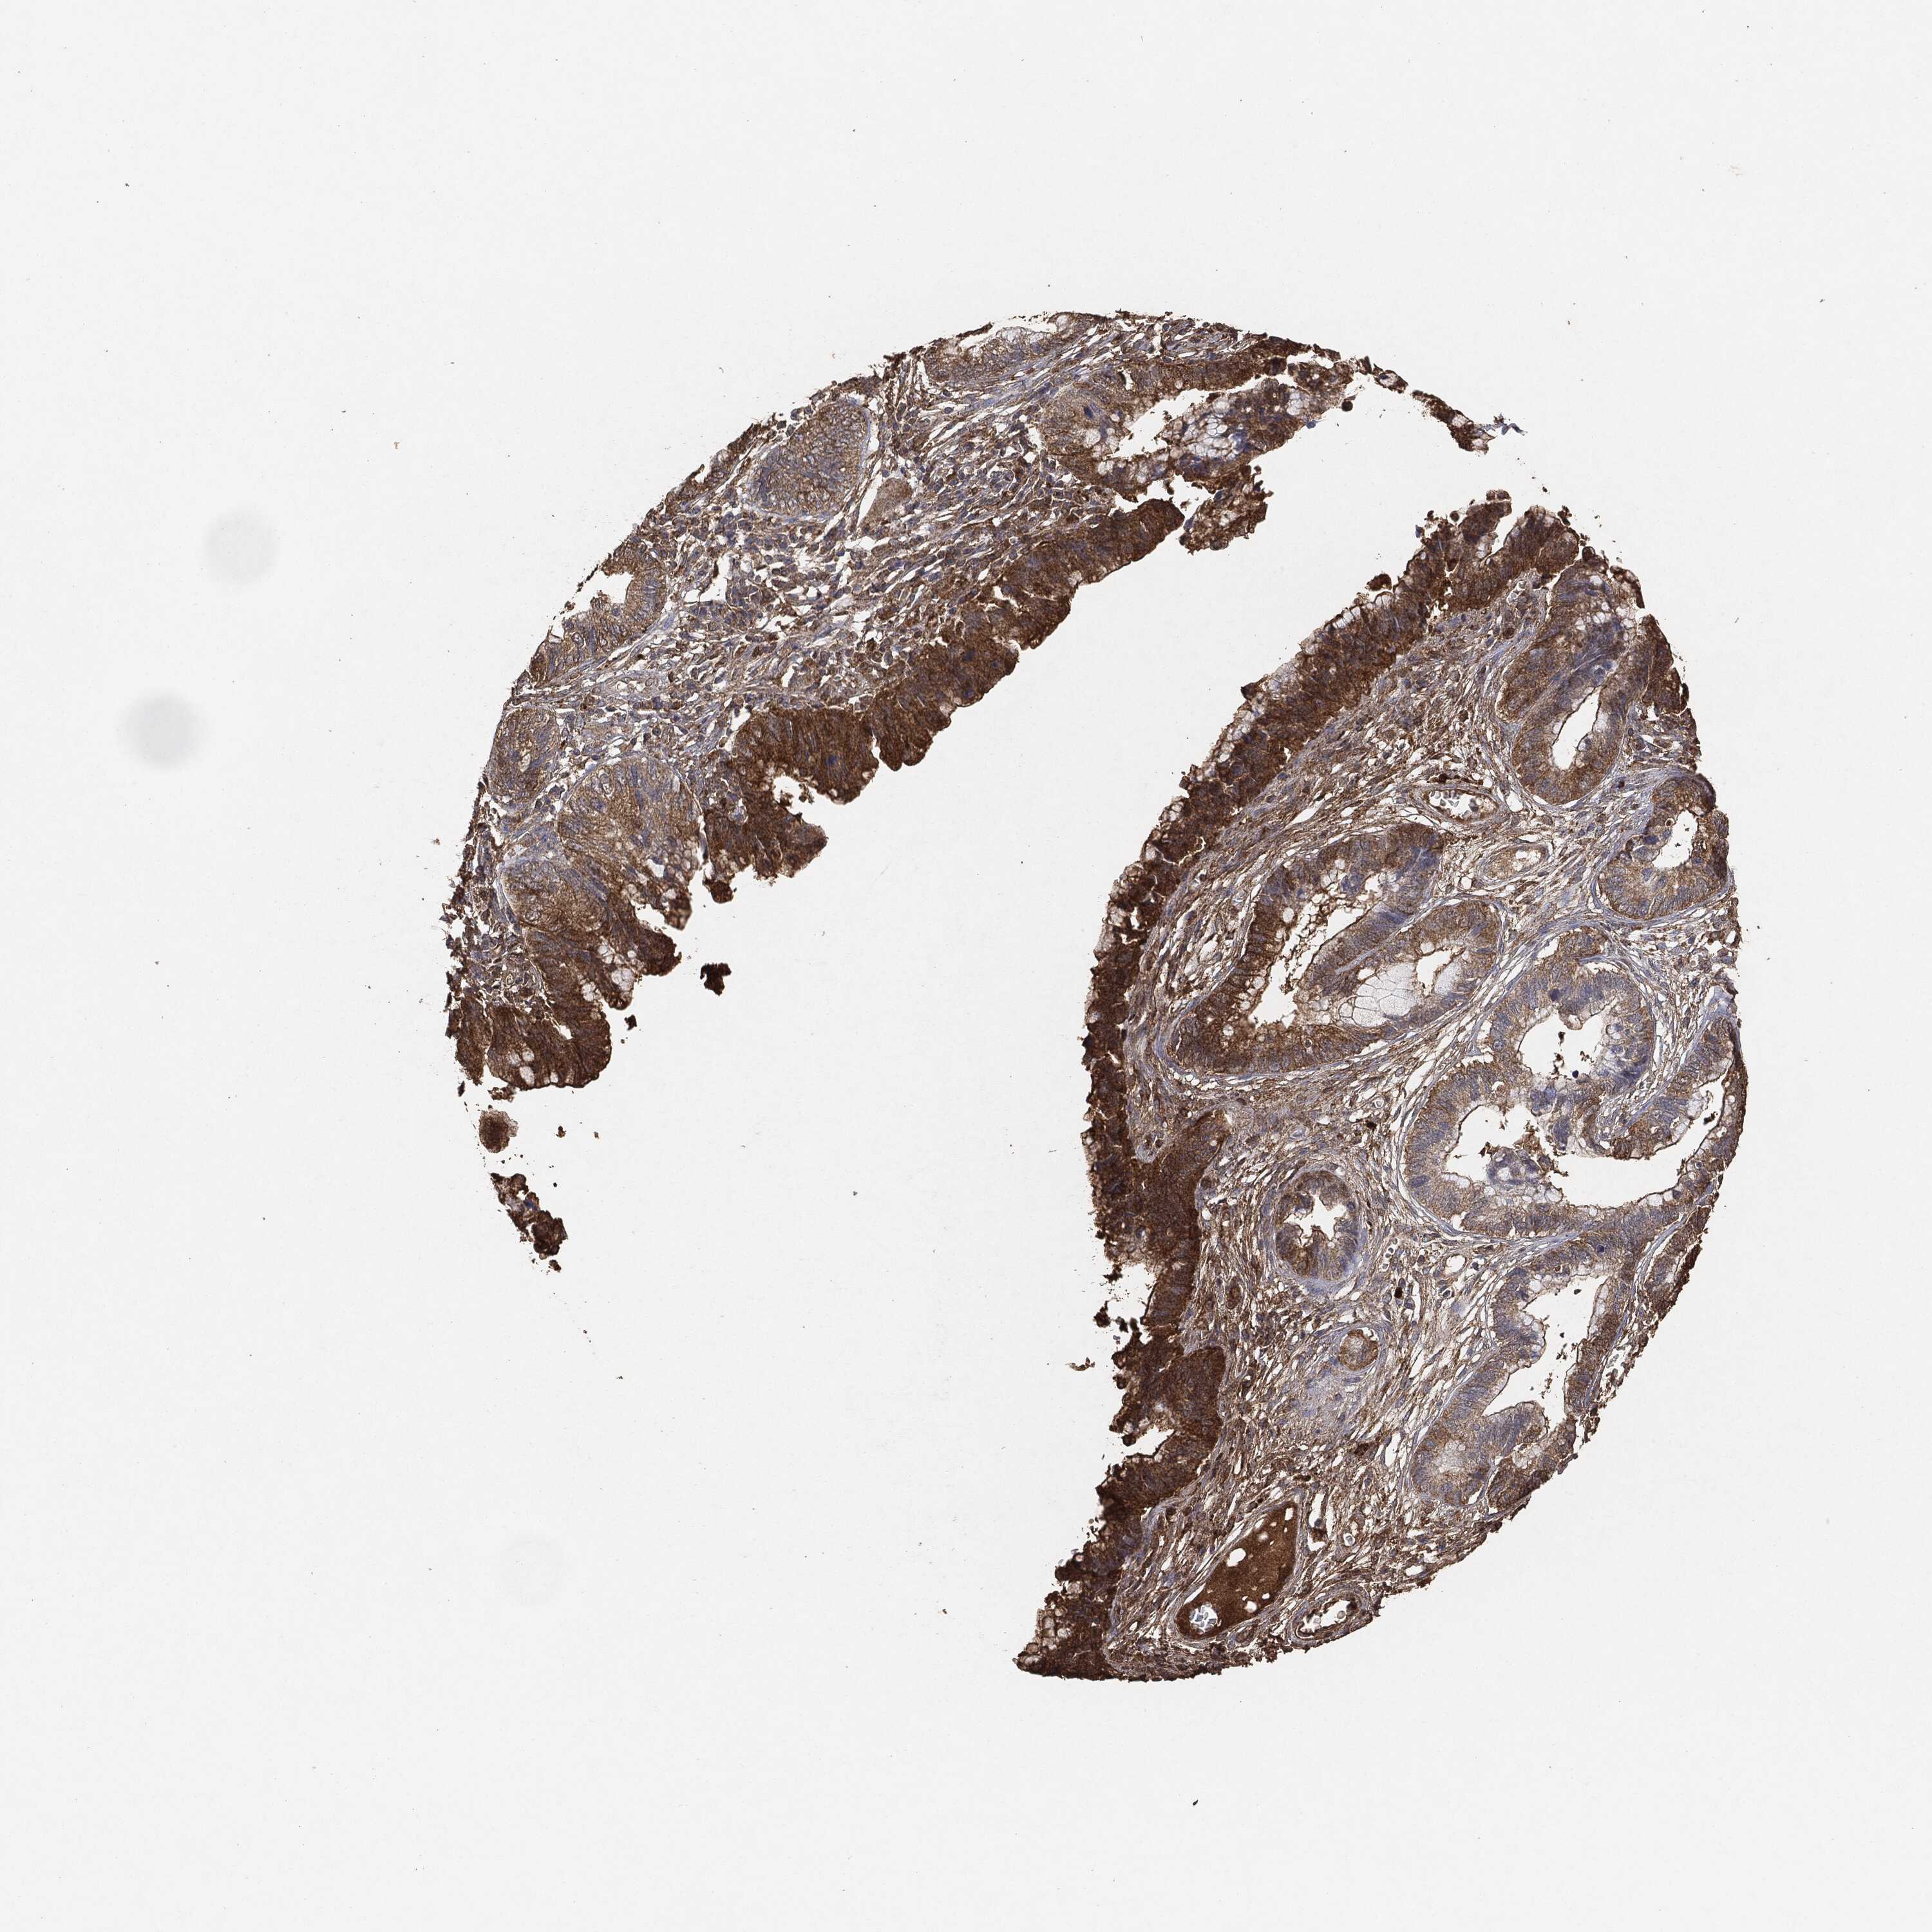

CERVICAL CANCER - Protein expressioni

A mouse-over function shows sample information and annotation data. Click on an image to view it in a full screen mode. Samples can be filtered based on level of antibody staining by selecting one or several of the following categories: high, medium, low and not detected. The assay and annotation is described here.

Note that samples used for immunohistochemistry by the Human Protein Atlas do not correspond to samples in the TCGA dataset.

Antibody stainingi

Antibody staining in the annotated cell types in the current human tissue is reported as not detected, low, medium, or high, based on conventional immunohistochemistry profiling in selected tissues. This score is based on the combination of the staining intensity and fraction of stained cells.

Each image is clickable and will lead to virtual microscopy that enables deeper exploration of all samples and also displays staining intensity scores, fraction scores and subcellular localization as well as patient and tissue information for each sample.

Staining

High

Medium

Low

Not detected

Intensity

Strong

Moderate

Weak

Negative

Quantity

>75%

75%-25%

<25%

None

Location

Nuclear

Cytoplasmic/membranous

Cytoplasmic/membranous,nuclear

Adenocarcinoma, NOS

Squamous cell carcinoma, NOS